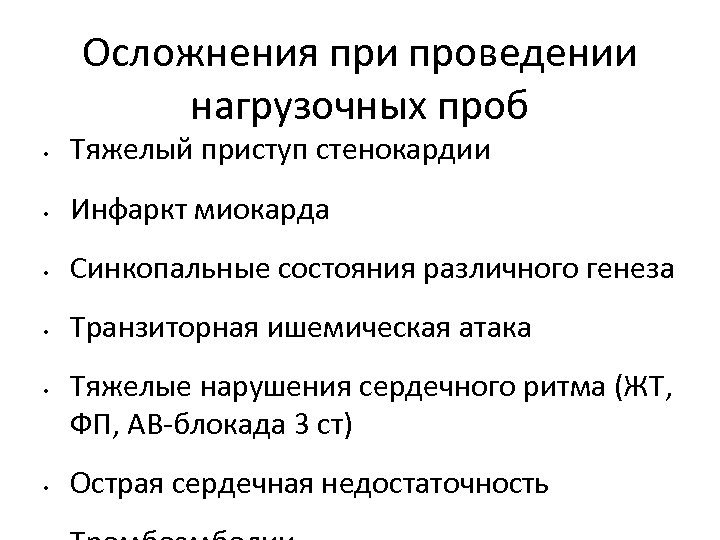

Осложнения при проведении нагрузочных проб • Тяжелый приступ стенокардии • Инфаркт миокарда • Синкопальные состояния различного генеза • Транзиторная ишемическая атака • • Тяжелые нарушения сердечного ритма (ЖТ, ФП, АВ-блокада 3 ст) Острая сердечная недостаточность

Осложнения при проведении нагрузочных проб • Тяжелый приступ стенокардии • Инфаркт миокарда • Синкопальные состояния различного генеза • Транзиторная ишемическая атака • • Тяжелые нарушения сердечного ритма (ЖТ, ФП, АВ-блокада 3 ст) Острая сердечная недостаточность